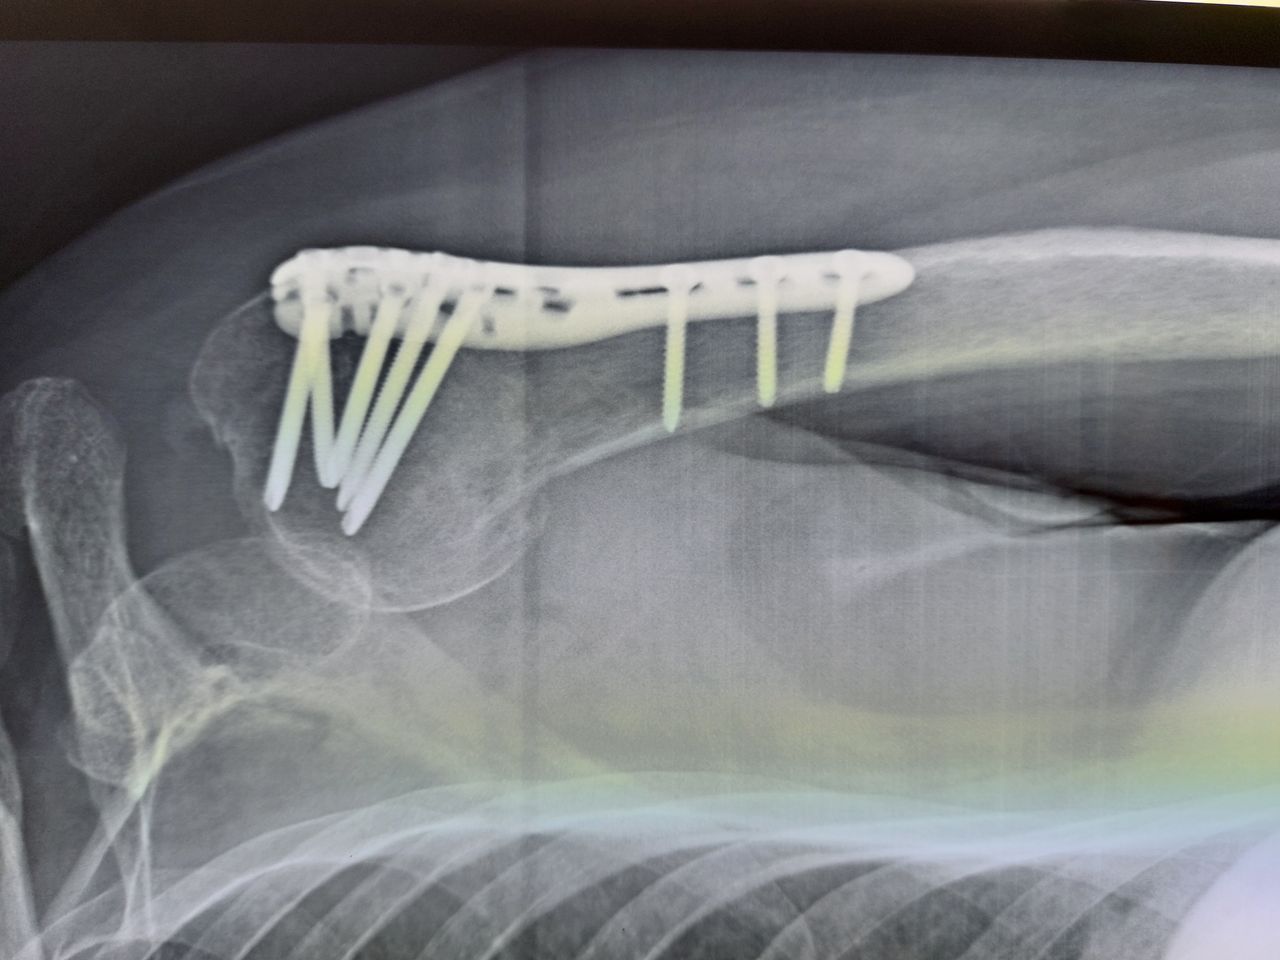

Conosco bene il Dr.Di Punzio,da circa venti anni, quando lo contattai per rimettere sù mia madre reduce di intevento al femore, già allora mi resi conto di molte sue qualità: professionalità, gentilezza e soprattuto empatia. Il 27 di ottobre per una caduta accidentale che mi ha compromesso spalla-braccio sx e cervicale, l'ho contattato e dopo varie sedute manuali e altro mi ha rimesso a nuovo. Dopo venti anni nutro per il Dr. Giovanni, fiducia per il suo lavoro e una grande empatia. E' un amico prezioso.